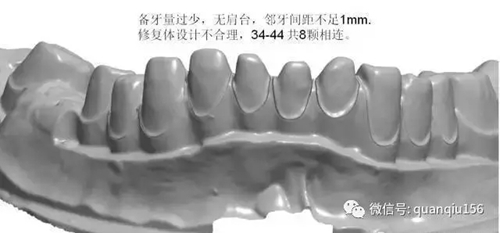

1、临床备牙不合理或基牙条件不适合做氧化锆

如:无肩台、凹面肩台、边缘线不清晰、双重边缘线、备牙空间不足、基牙有倒凹或牙桥没有共同就位道、基牙切端或颌缘过于尖锐等等。